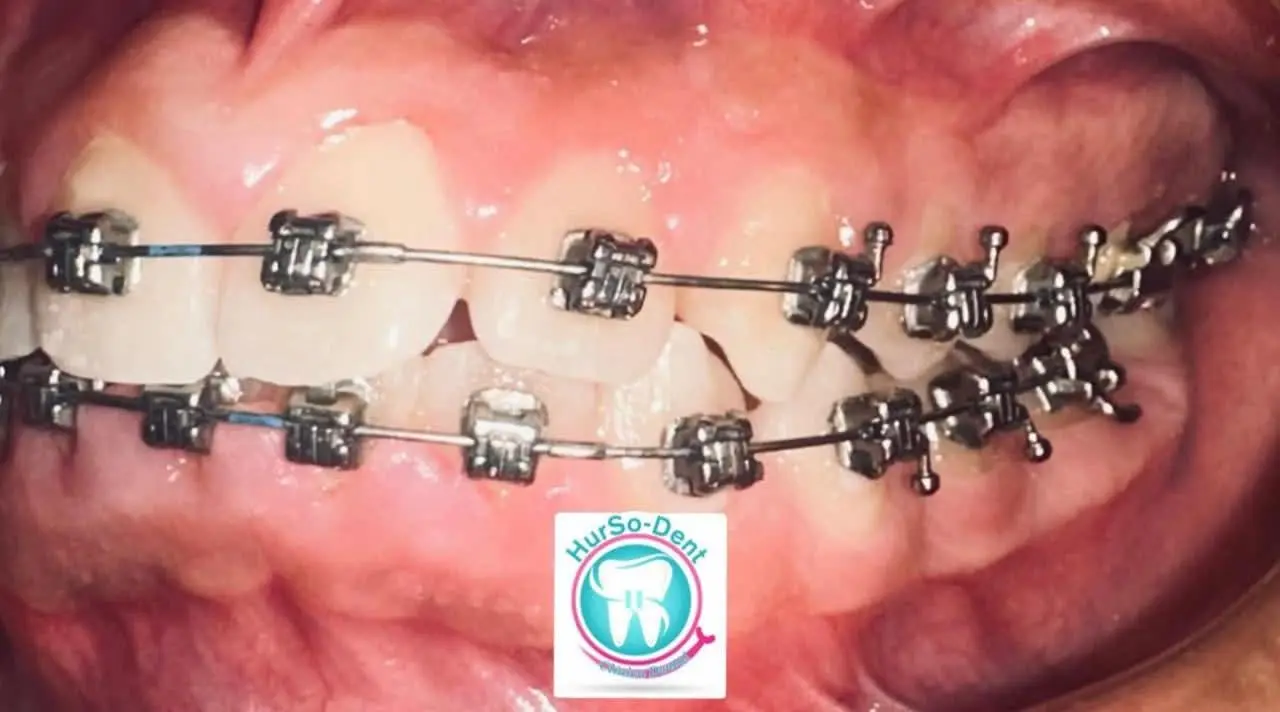

Corregimos la posición de los dientes y la mordida para lograr una sonrisa armónica y una función dental óptima. Este tratamiento, realizado por un especialista en Ortodoncia, transformara tu sonrisa y evitara problemas futuros en tu salud bucal.

Agenda tu citaOrtodoncia(Brackets)